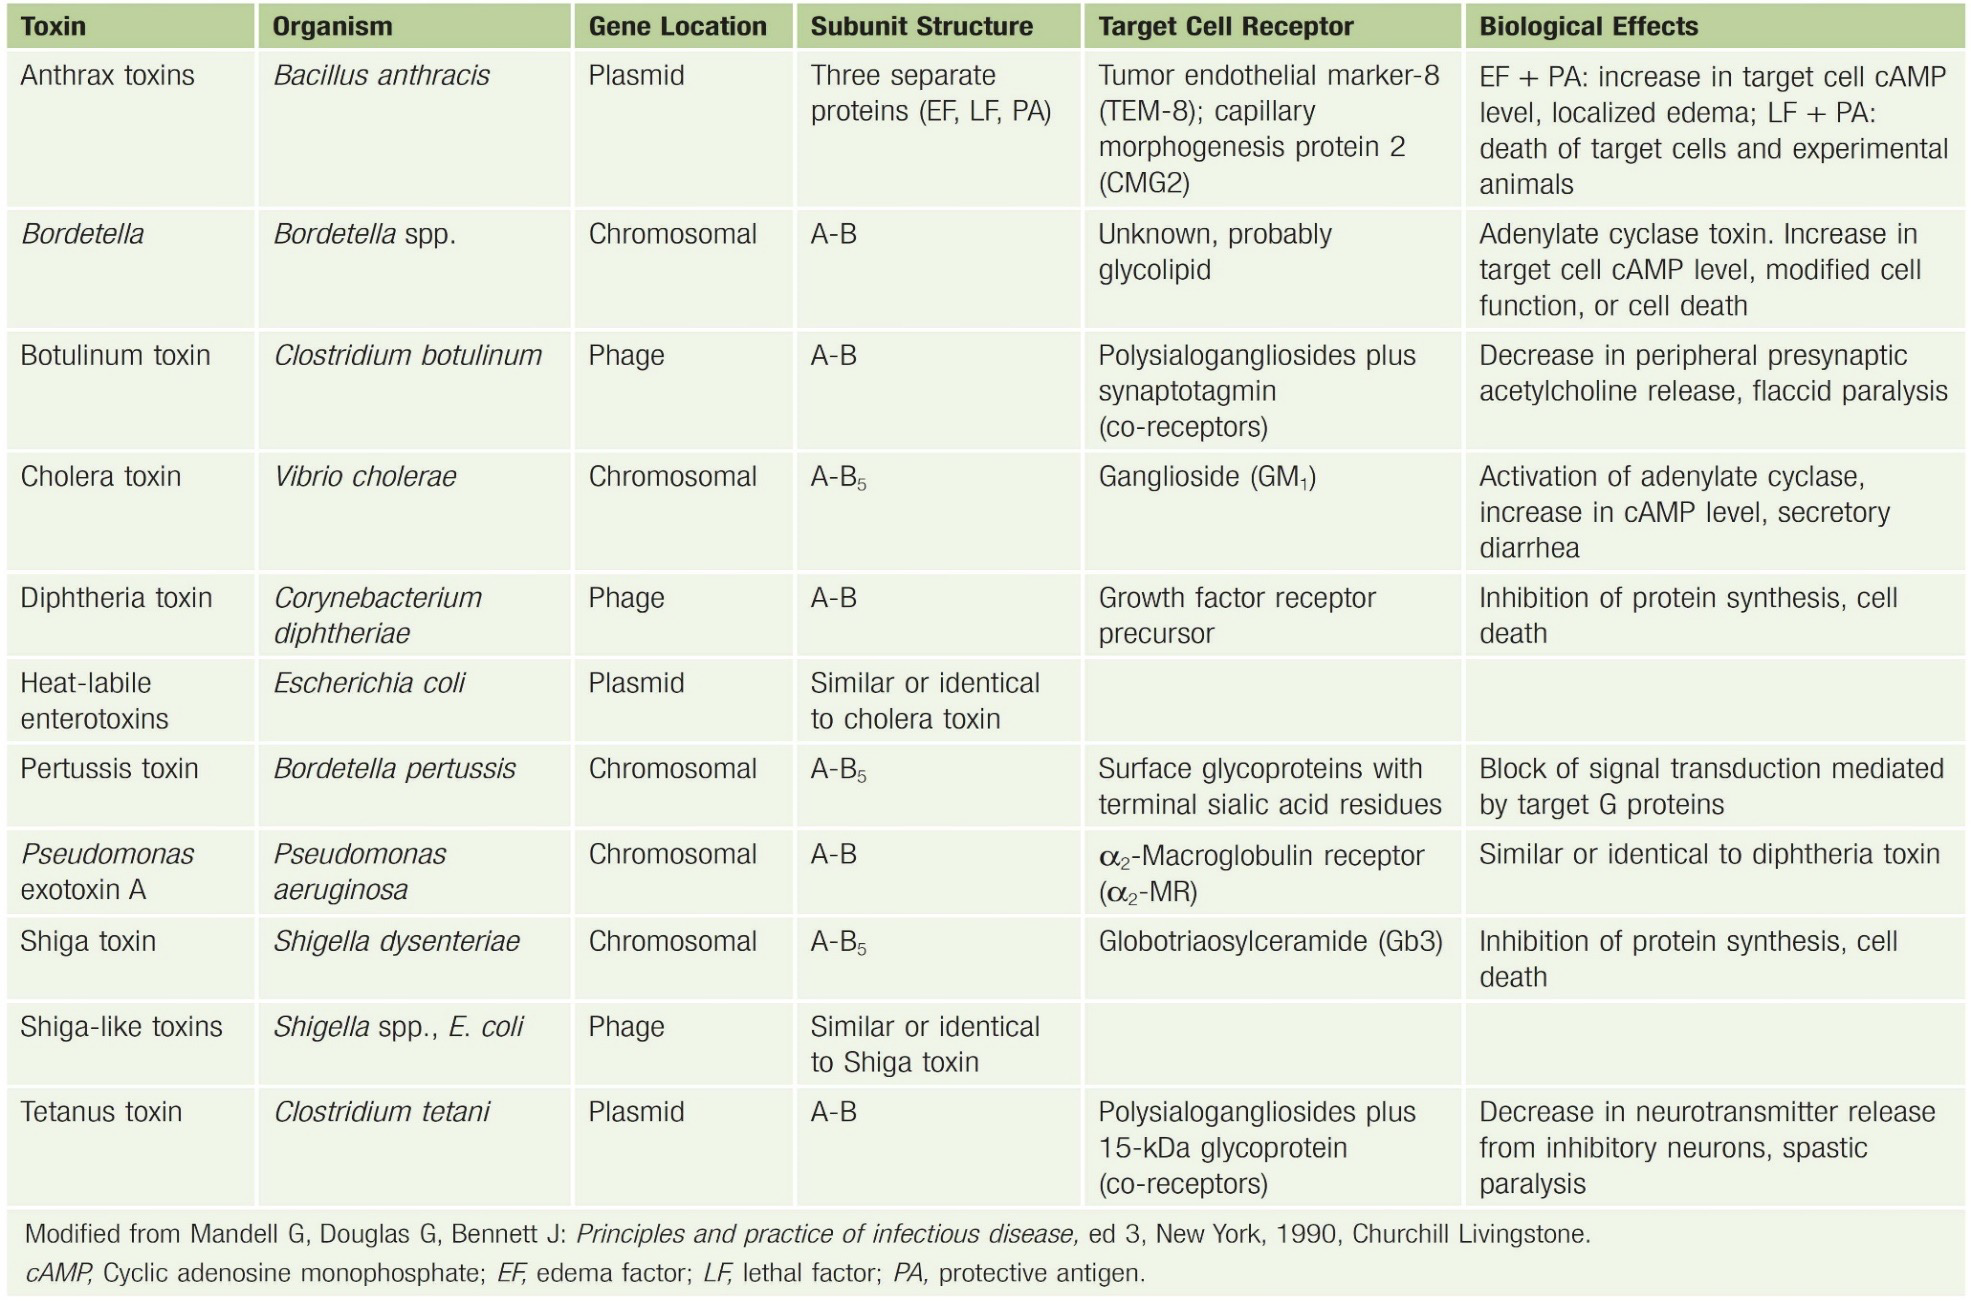

A-B exotoxin

- B for bounding, A for action

都要背。。。

Bacillus anthracis (炭疽桿菌, G+)

- 3 proteins

- Protective Antigen(PA83): B toxin

- Edema factor : 水腫, A toxin

- Lethal factor :致命,殺細胞,A toxin

- 2 exotoxin

- Edema toxin = PA63+EF

- Lethal toxin = PA63+LF

AB toxin

| 毒素 | 機制 | 菌種 |

|---|---|---|

| Edema toxin | cAMP ↑ | B. Anthracis |

| cholera toxin (霍亂毒素) |

cAMP ↑ | Vibrio cholera |

| Bacillus cereus Diarrheal form |

cAMP ↑ | B. cereus |

| Shiga toxin | 60S 核醣體的28S rRNA,apoptosis | Shigella, EHEC |

| Lethal toxin | apoptosis | B. Anthracis, |

| Diphtheria toxin (白喉毒素) |

轉譯(EF2) | Cotynebacterium diphtheria |

| exotoxin A | Pseudomonas aeruginosa | |

| Pertussis toxin | cAMP↑ | Bordetella pertussis (百日咳) |

| Tetanospasmin | Block GABA | Clostridium tetani |